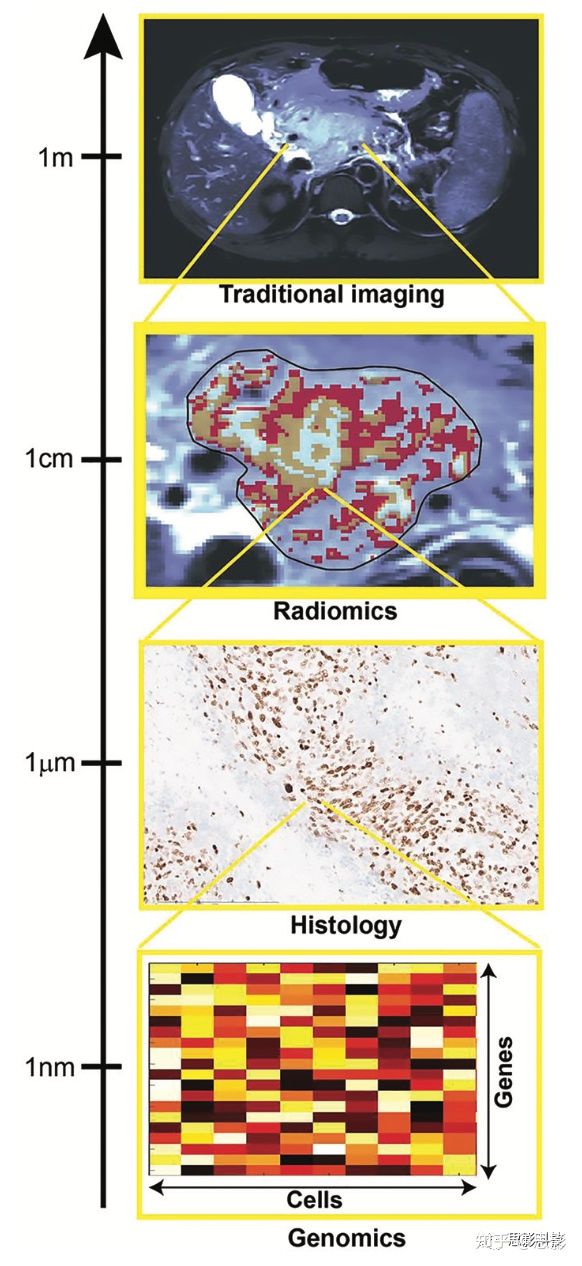

现代医学得益于大量的测量技术,这些技术能够告知医生可能通过肉眼检查无法直接获得的疾病特征。生物过程可以在空间尺度上进行跟踪,从个体的水平一直到单个分子,成像方法覆盖了这一范围的大部分。影像成像主要基于解剖和代谢成像,如图1所示。通过在所用成像技术分辨率范围内的空间尺度上直接量化肿瘤成像表型,影像组学旨在提供对疾病多方面、间接洞察,包括肿瘤分级、组织学和遗传亚型以及预测结果。这些特征反映了在不同空间尺度上发生的变化。因此,在大多数研究中,能够进行影像组学预测的间接关系的生物学机制在很大程度上仍然无法解释。重要的是,由于影像组学数据可以纵向获得,因此可以用来量化潜在“生物特性”对外部扰动的响应。

图1,图中显示了多尺度量化提供互补的肿瘤分析。

组织学和基因组分析可以提供特定的小规模分析,有助于验证影像组学结果,重点是量化尺寸超过图像分辨率的空间模式。